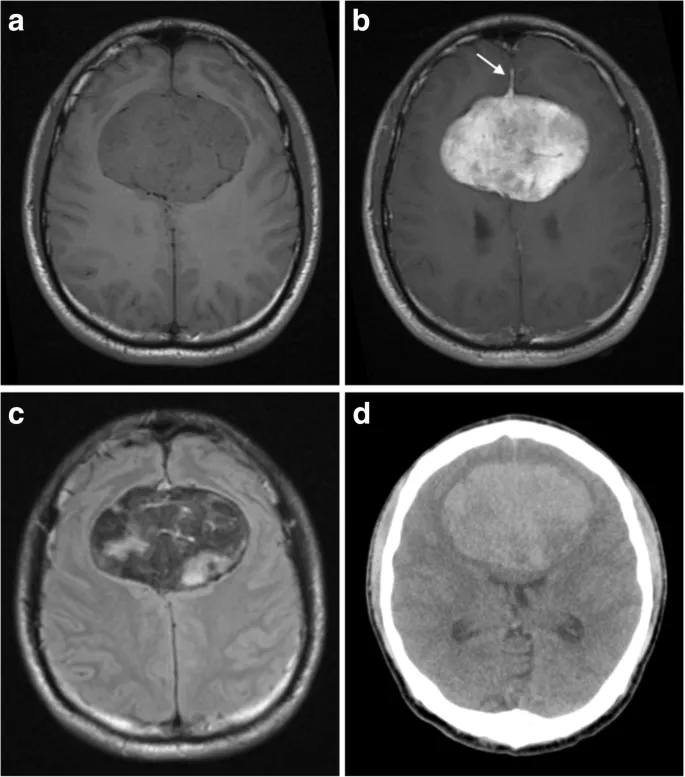

⭐ High-Yield: Glioblastoma often arises in the cerebral hemisphere and can cross the corpus callosum, creating a "butterfly glioma" appearance on imaging.

- Glioblastoma is the most common and aggressive adult primary tumor, showing a butterfly appearance and pseudopalisading necrosis.